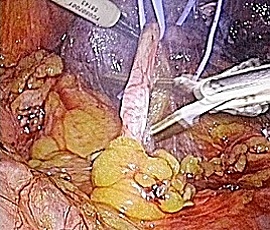

手術画像